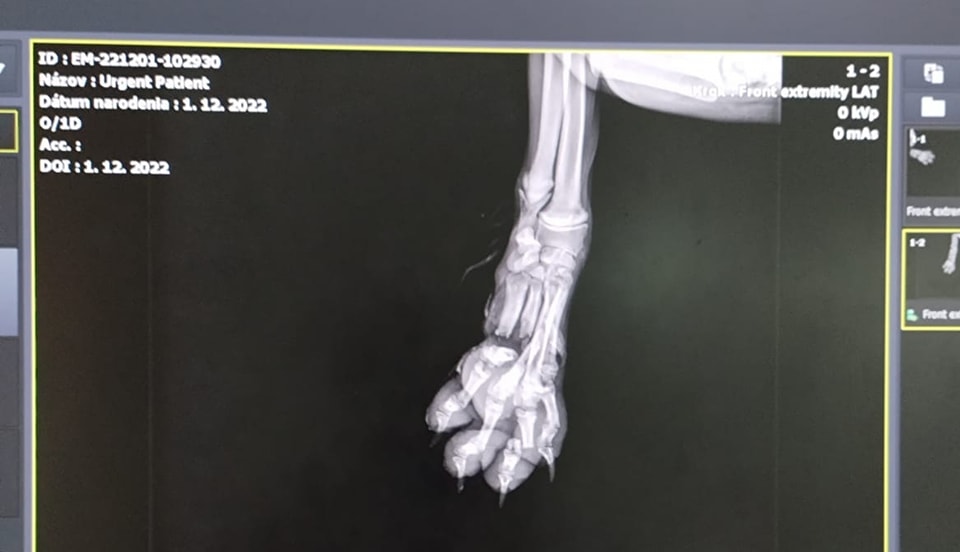

Další psík s pár zlomeninami na nôžke.